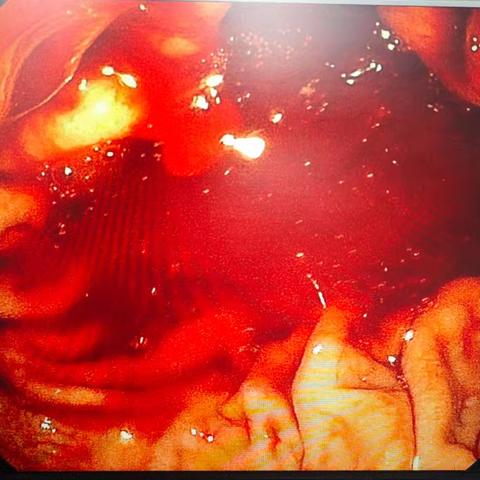

枣核虽小,能伤脏腑;胃镜妙手,化险为夷——24小时内镜急救,守护消化道安全!